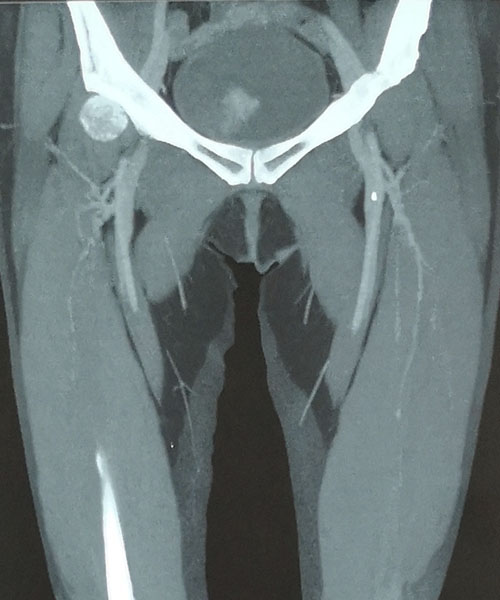

术前CTV评估股静脉及分支